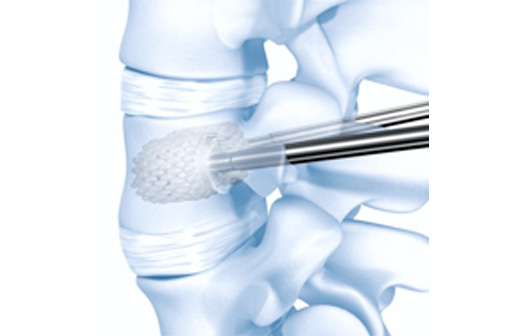

Percutaneous kyphoplasty Puncture Instruments Set, Spine Surgical Balloon Catheter Injection Tool

Product Features

| 1 | Minimally invasive surgery, less harm to body tissue, less bleeding |

| 2 | Easy operation procedures, shorter time (about 40 minutes) |

| 3 | Quick to recover, effectiveness (release pain and reinforce damaged vertebral body immediately after operation, improve the ability of activity) |

Application

1. Patient with vertebral compression fracture due to osteoporosis

2. Vertebral Tumor

Osteolytic meta static carcinoma of vertebra body

Myeloma and hemangioma